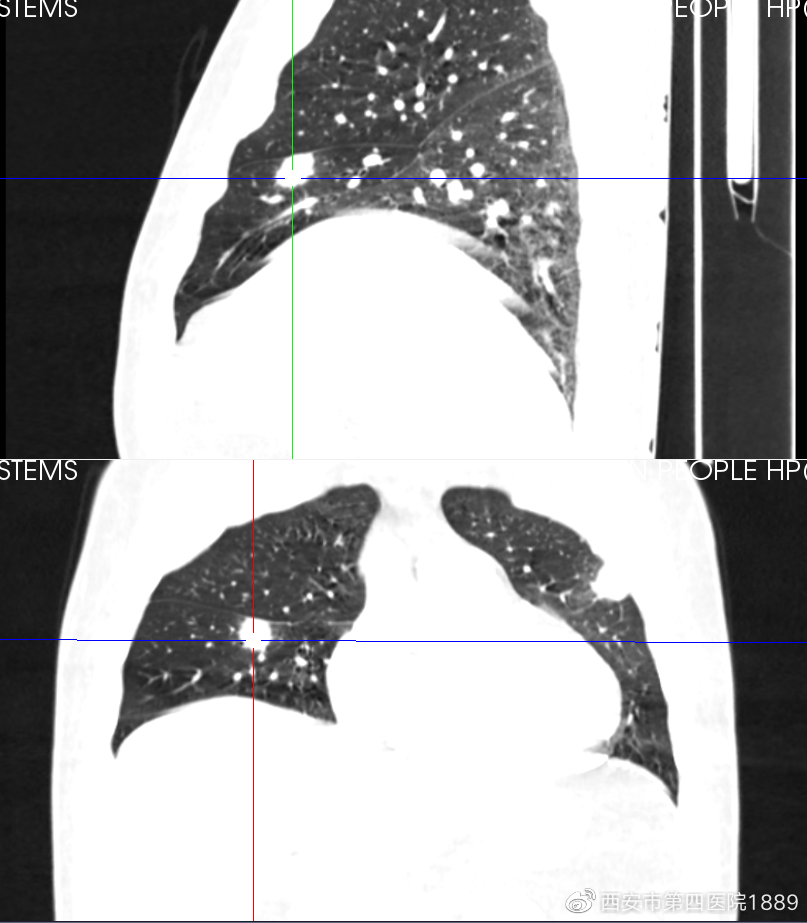

胸部CT平扫:右肺上叶后段胸膜下可见一微结节,直径约3mm;右肺中叶可见一实性结节影,大小约1.4cm×1.2cm

经医师询问,患者无发热、咳嗽咳痰、胸闷喘息、胸痛等呼吸系统症状;体格检查胸廓对称,呼吸频率正常,两肺触诊和听诊均阴性;血常规基本正常,肿瘤标志物未见明显异常。从胸部影像学(LDCT)来看,患者左肺上叶呈支气管周围分布,伴有晕征,考虑炎症可能性大,而右肺中叶病灶呈结节样,周围可见毛刺征和血管集束征,不能排除原发性肺部肿瘤可能。

为了更好的了解病灶性质,需全方面观察结节形态、內部组织、血管关系等特点进行判断良恶性。通过CT图像后处理技术联合增强CT,得到病灶的多平面成像,进而从多个角度观察病灶特点,并观察病灶和血管的关系以及强化程度。

胸部增强ct三位重建,先后为矢状位及冠状位。

通过多平面重建技术,先前右肺中叶在轴位呈现球星结节影,在矢状位及冠状位呈宽基底紧邻胸膜,未见明显胸膜增厚及牵拉,这是良性的表现。但是增强影像可见血管进入,需进一步观察病灶的内部情况。通过DWI(磁共振检查的一种方法)检查发现,患者双侧病灶ADC(抗体-药物结合物)呈高信号,证明该病灶为良性(炎症可能性大)。患者仅需口服莫西沙星1周,1月后复查胸部CT即可。